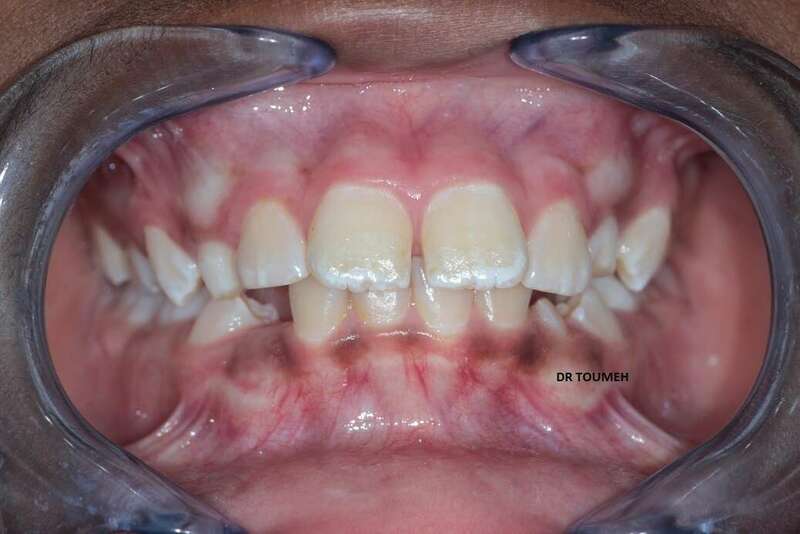

Le traitement Orthodontique doit commencer au bon moment le plutôt possible,

Avant

Après

Votre Orthodontiste détermine le moment où il faut entamer le traitement orthodontique selon plusieurs paramétres (l'age de l'enfant, l'age osseux, le cas et le plan de traitement .....).